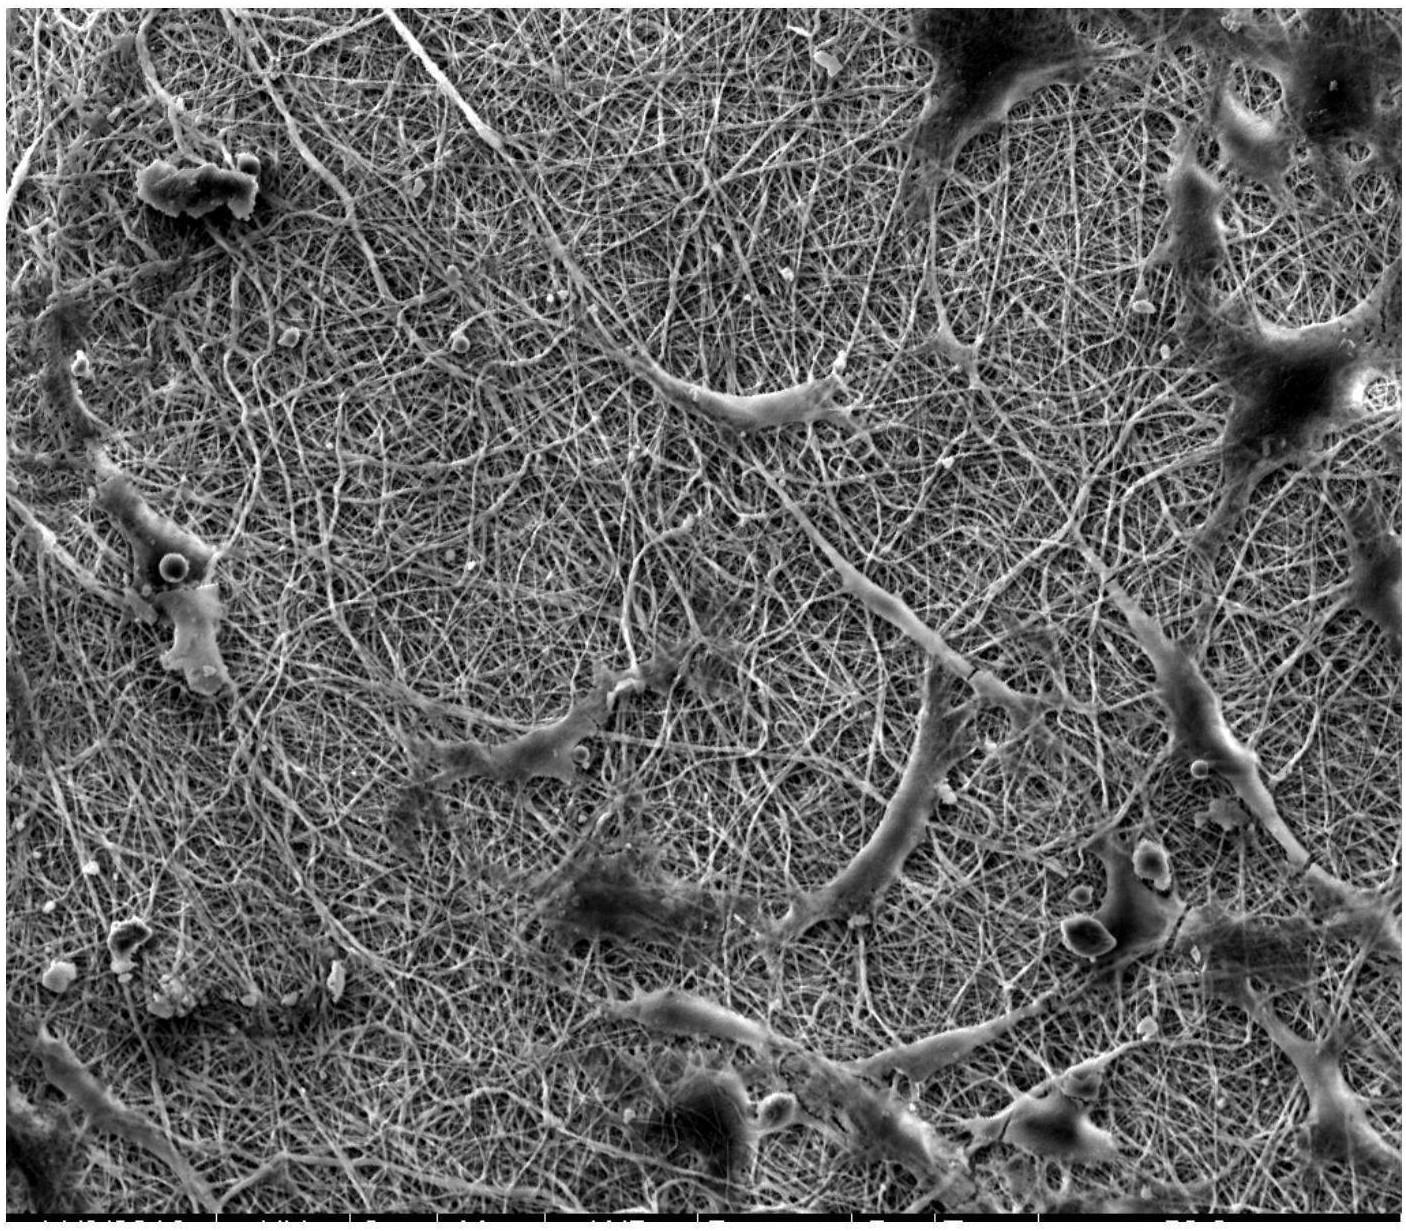

图7 纳米硅酸盐浓度1%的骨诱导膜MC3T3-e1细胞粘附状态扫描电镜图;